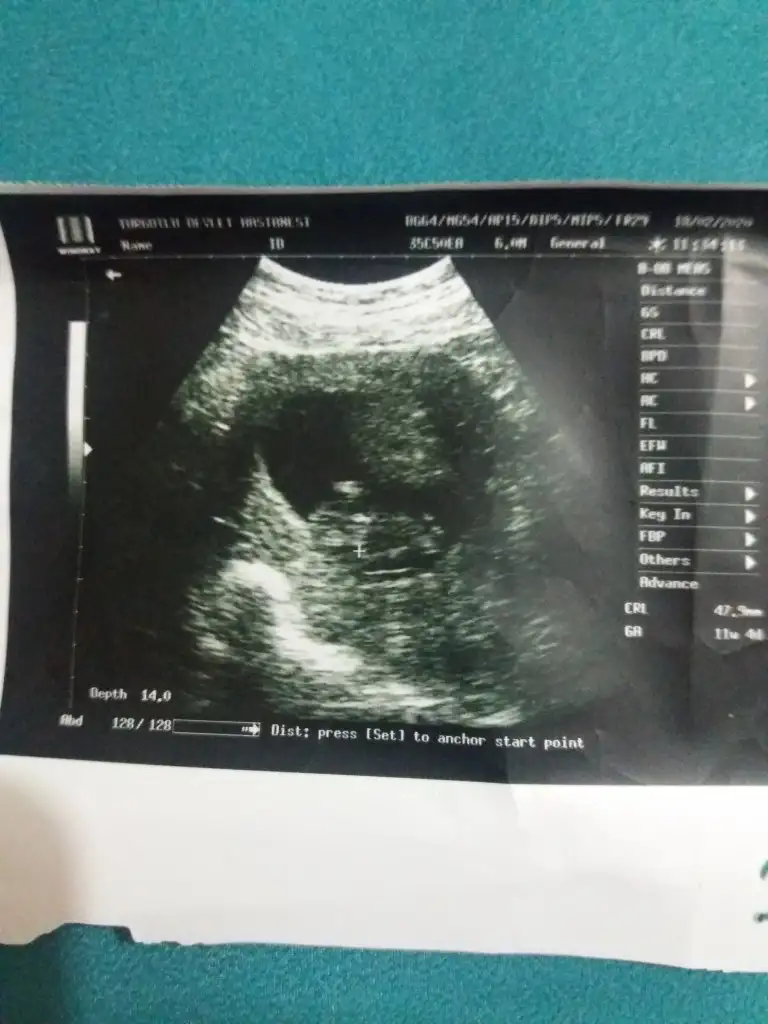

En net görüntüsü bu maalesef şimdilik. Doktor da erkeğe benziyor dedi ama erken olduğu için yüzde yüz diyemedi ama ben net bir pipi gördüm dedi. 10 gün sonra netleşecek bakalım ama oradaki parlaklığı ben de pipi olarak değerlendiriyorum o yüzden kesin gözüyle baktım erkeğeSanki pipi var gibi yanlış mı gördüm acaba![]()

Ben normalde anlamam hiçEn net görüntüsü bu maalesef şimdilik. Doktor da erkeğe benziyor dedi ama erken olduğu için yüzde yüz diyemedi ama ben net bir pipi gördüm dedi. 10 gün sonra netleşecek bakalım ama oradaki parlaklığı ben de pipi olarak değerlendiriyorum o yüzden kesin gözüyle baktım erkeğe![]()